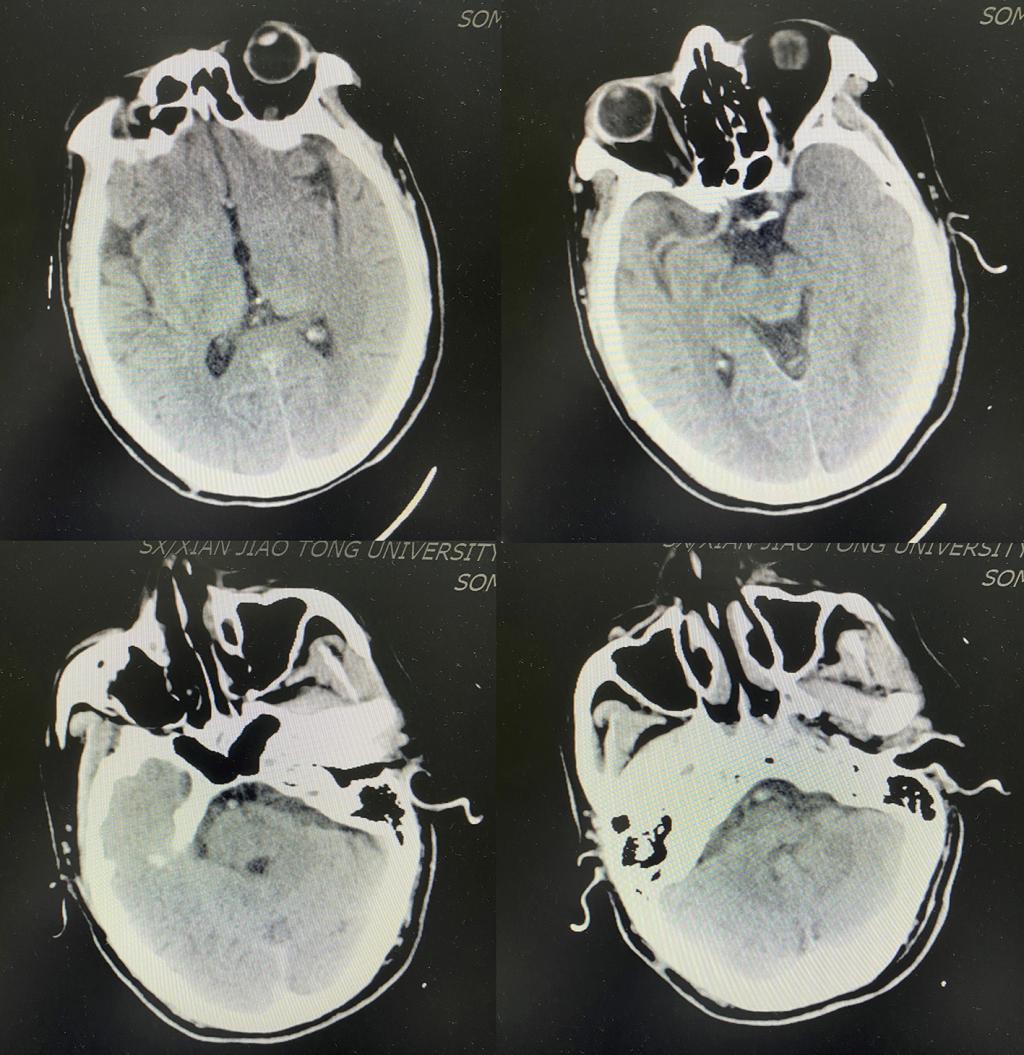

颅脑DWI示左侧小脑半球、左侧颞叶、双侧枕叶急性脑梗死

此时,患者的意识状态进一步恶化,呼之不应,肢体瘫痪,间断呕吐胃内容物,双侧眼球部分凝视,双侧瞳孔不等大,左侧瞳孔6mm,右侧2.5mm,对光反射均迟钝,神经系统NIHSS评分已经达到20分(NIHSS评分>15分为中重度卒中,分数越高提示神经受损越严重)。

结合患者的临床症状及影像学资料,当日值班二线范清雨主治医师迅速意识到患者符合基底动脉尖综合征,这是一种临床表现复杂多样,病情危重,且预后差,致残率、死亡率高的特殊缺血性脑血管疾病。此时此刻,对患者而言,时间就是大脑,时间就是生命。脑血管开通越早,患者恢复的希望就越大。